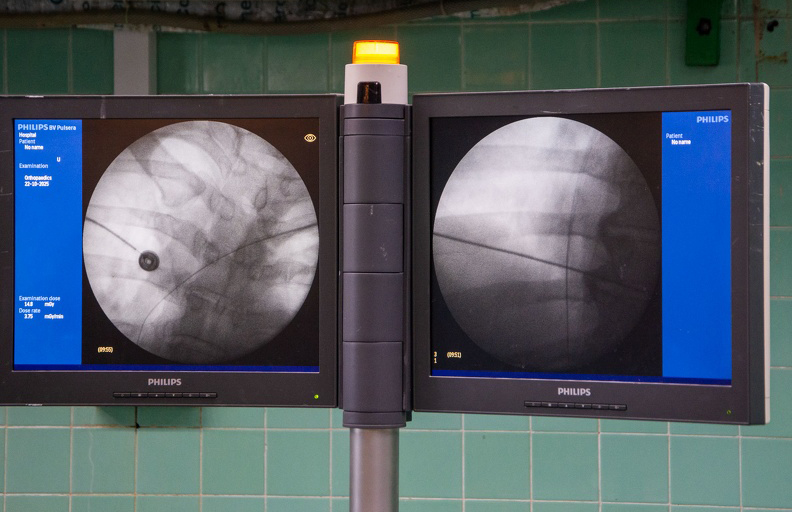

La manera de implantación del DAI es bastante parecida a la del marcapasos, pero los electrodos son más gruesos; se coloca dentro del corazón, detecta la arritmia y en dependencia de la duración y la frecuencia la choca o le da una terapia que se llama ATP, explicó a la prensa Mengana Betancourt.

En Pinar del Río normalmente se ponen marcapasos, pero es la primera vez que se instala este equipo, apuntó la doctora Maylín Vilaú Jiménez, especialista en segundo grado de Cardiología del «Abel Santamaría Cuadrado» y una de las que participó en la intervención.

Se trata de un honor y un reto para nuestra institución porque procederes como DAI o estimulación cardíaca que se realizan en el Instituto de Cardiología y Cirugía Vascular son con un sistema de electrofisiología con el cual no contamos en la provincia, acotó.

Edel Ferro, de 47 años de edad, fue el beneficiario de la intervención quirúrgica, quien había sufrido arritmias malignas en un corazón estructuralmente enfermo, según Mengana Betancourt.

A pesar de que el abordaje para poder entrar al corazón fue un poco complicado se logró sin problemas y la operación resultó un éxito, aseveró la especialista, e indicó que el paciente permanecerá 72 horas hospitalizado para supervisar y prevenir procesos infecciosos.